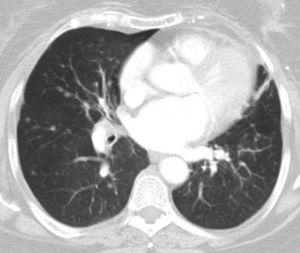

She had a history of chronic cough for many years. Lung function tests showed forced vital capacity of 1820cm3 (80.5%) and a forced expiratory volume in 1 second of 1120cm3 (59.6%), ratio 61.33%. CT revealed multiple nodules of different sizes distributed throughout both lung fields. Six months later, the number and size of the nodules had increased (Fig. 1).

Positron emission tomography (PET)-CT revealed solid nodules measuring between 8 and 14mm, with maximum SUV of 3.88. Others showed no uptake. Three enlarged lymph nodes were also observed with maximum SUV of 6.8–8.0mm in the right cervical and retromandibular region. Bronchoscopy provided no significant information, with the exception of Aspergillus fumigatus growth in the bronchial aspirate which subsequently became negative. Two months later, a video-assisted thoracoscopy with wedge resections of the middle and lower right lobe showed diffuse idiopathic neuroendocrine cell hyperplasia associated with tumorlets and peripheral typical carcinoid tumors (Fig. 2).